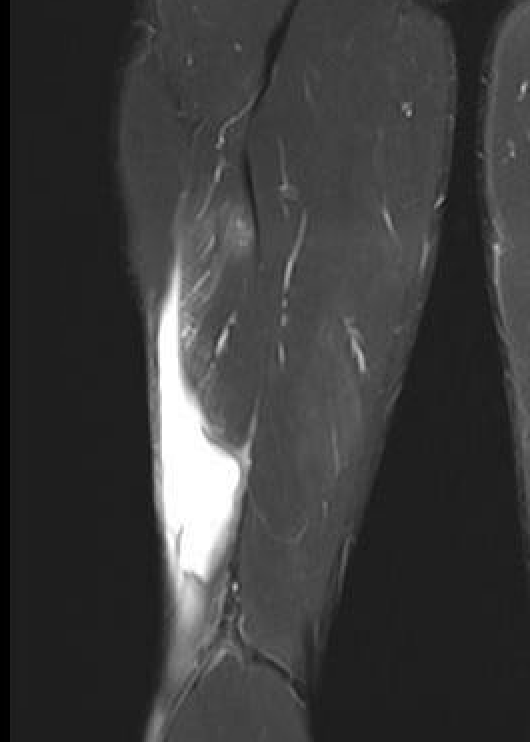

Grade 4 distal biceps femoris T Junction musculotendinous tear